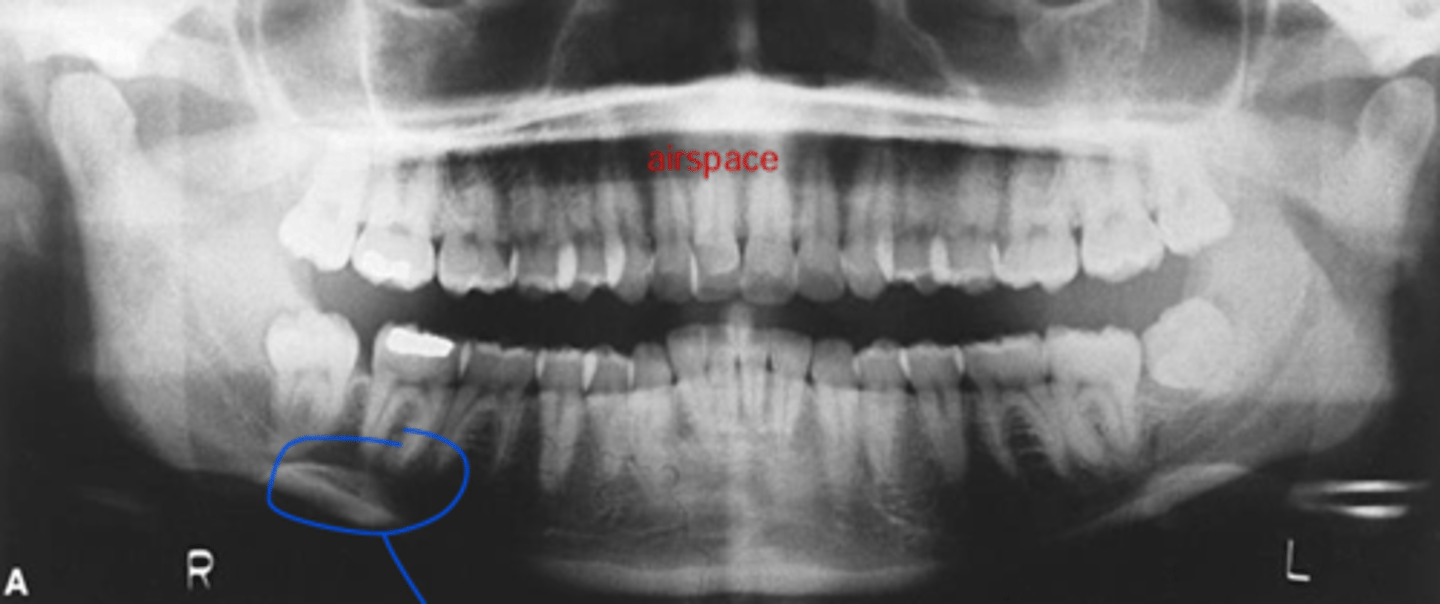

patient is too close to sensor

What is the problem with the patient's positioning in this image?

- patient didn't close all the way

- chin was down

- patient is too close to the film/receptor

What are the problems in this panoramic image?

What is the structure circled in blue?